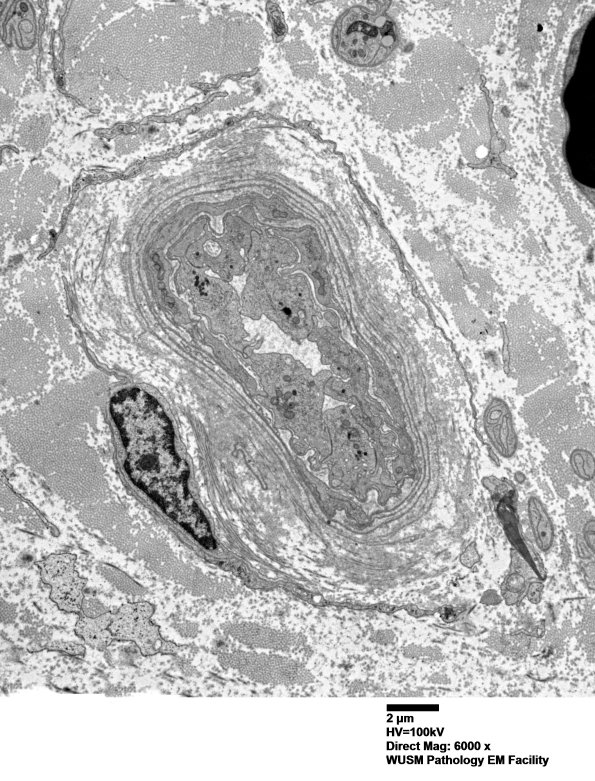

16B1,2 Accumulated mostly intact basal membranes (arrows, 16B2) expand the vessel wall. (electron micrographs)